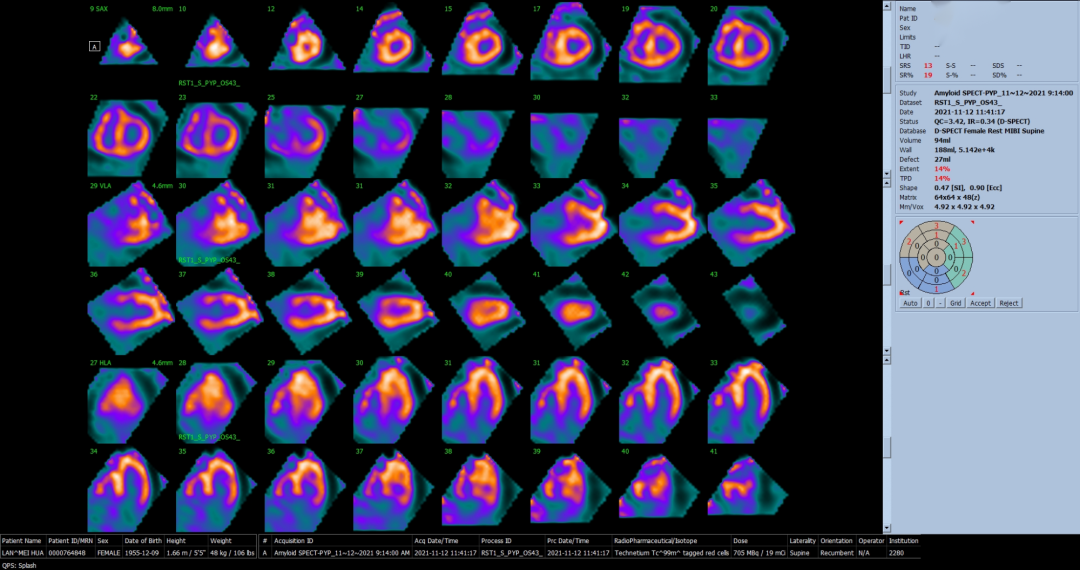

▲ 患者的核素显像

既往诊断ATTR-CA需要进行心肌活检,但这是一个有创检查,患者检查意愿低,且具有一定的风险,这就需要一个快速和高度敏感和特异的无创诊断工具。而D-SPECT是一种基于固态检测器的新型心脏专用检测系统, 目前广泛应用于心肌灌注显像。Uzair Mahmod[1]团队升级了D-SPECT使用相关图像采集和处理软件,能可靠地用于转甲状腺素蛋白心脏淀粉样变(ATTRCA)的诊断。

通过单中心分析显示,与传统ECT平面扫描相比,D-SPECT在诊断ATTR上具有可比性。D-SPECT优点还包括紧凑性、以区域为中心的扫描,更高的灵敏度和更高的分辨率。此外,D-SPECT直立采集更具优势,它的设计对于那些由于充血性心力衰竭或肥胖而无法平躺的传统γ相机系统的患者是最佳的选择。

本文中的这位患者,后来又做了心脏磁共振(CMR)提示左右心室心肌增厚合并心内膜下弥漫性延迟强化,轻链检测阴性。为了进一步分型,血液被送检,检测到异常单克隆免疫球蛋白。接着病人做了99锝焦磷酸盐(99m Technetium-pyrophosphate)核素扫描。这项检查对ATTR 淀粉样变性的特异性可以高达97%。结果显示该患者的心脏呈强阳性改变。根综合该患者临床及检查结果,ARRT的诊断明确。为进一步分型,进行基因检测,检测出至ATTR的但基因突变,故该患者最终诊断突变型ATTR明确。该患者的弟弟也进行了D-SPECT扫描及基因检测,最终诊断突变型ATTR,其突变位点与其姐姐一致。